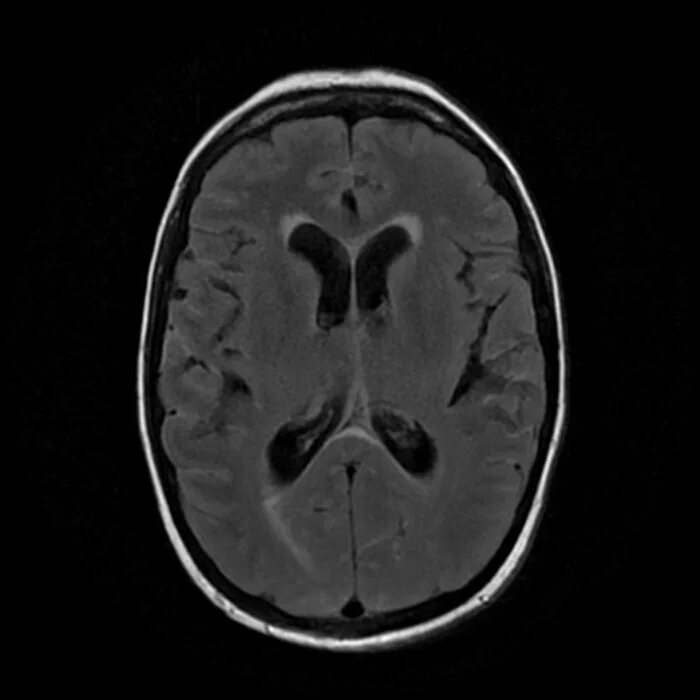

Умеренное расширенное субарахноидальное пространство